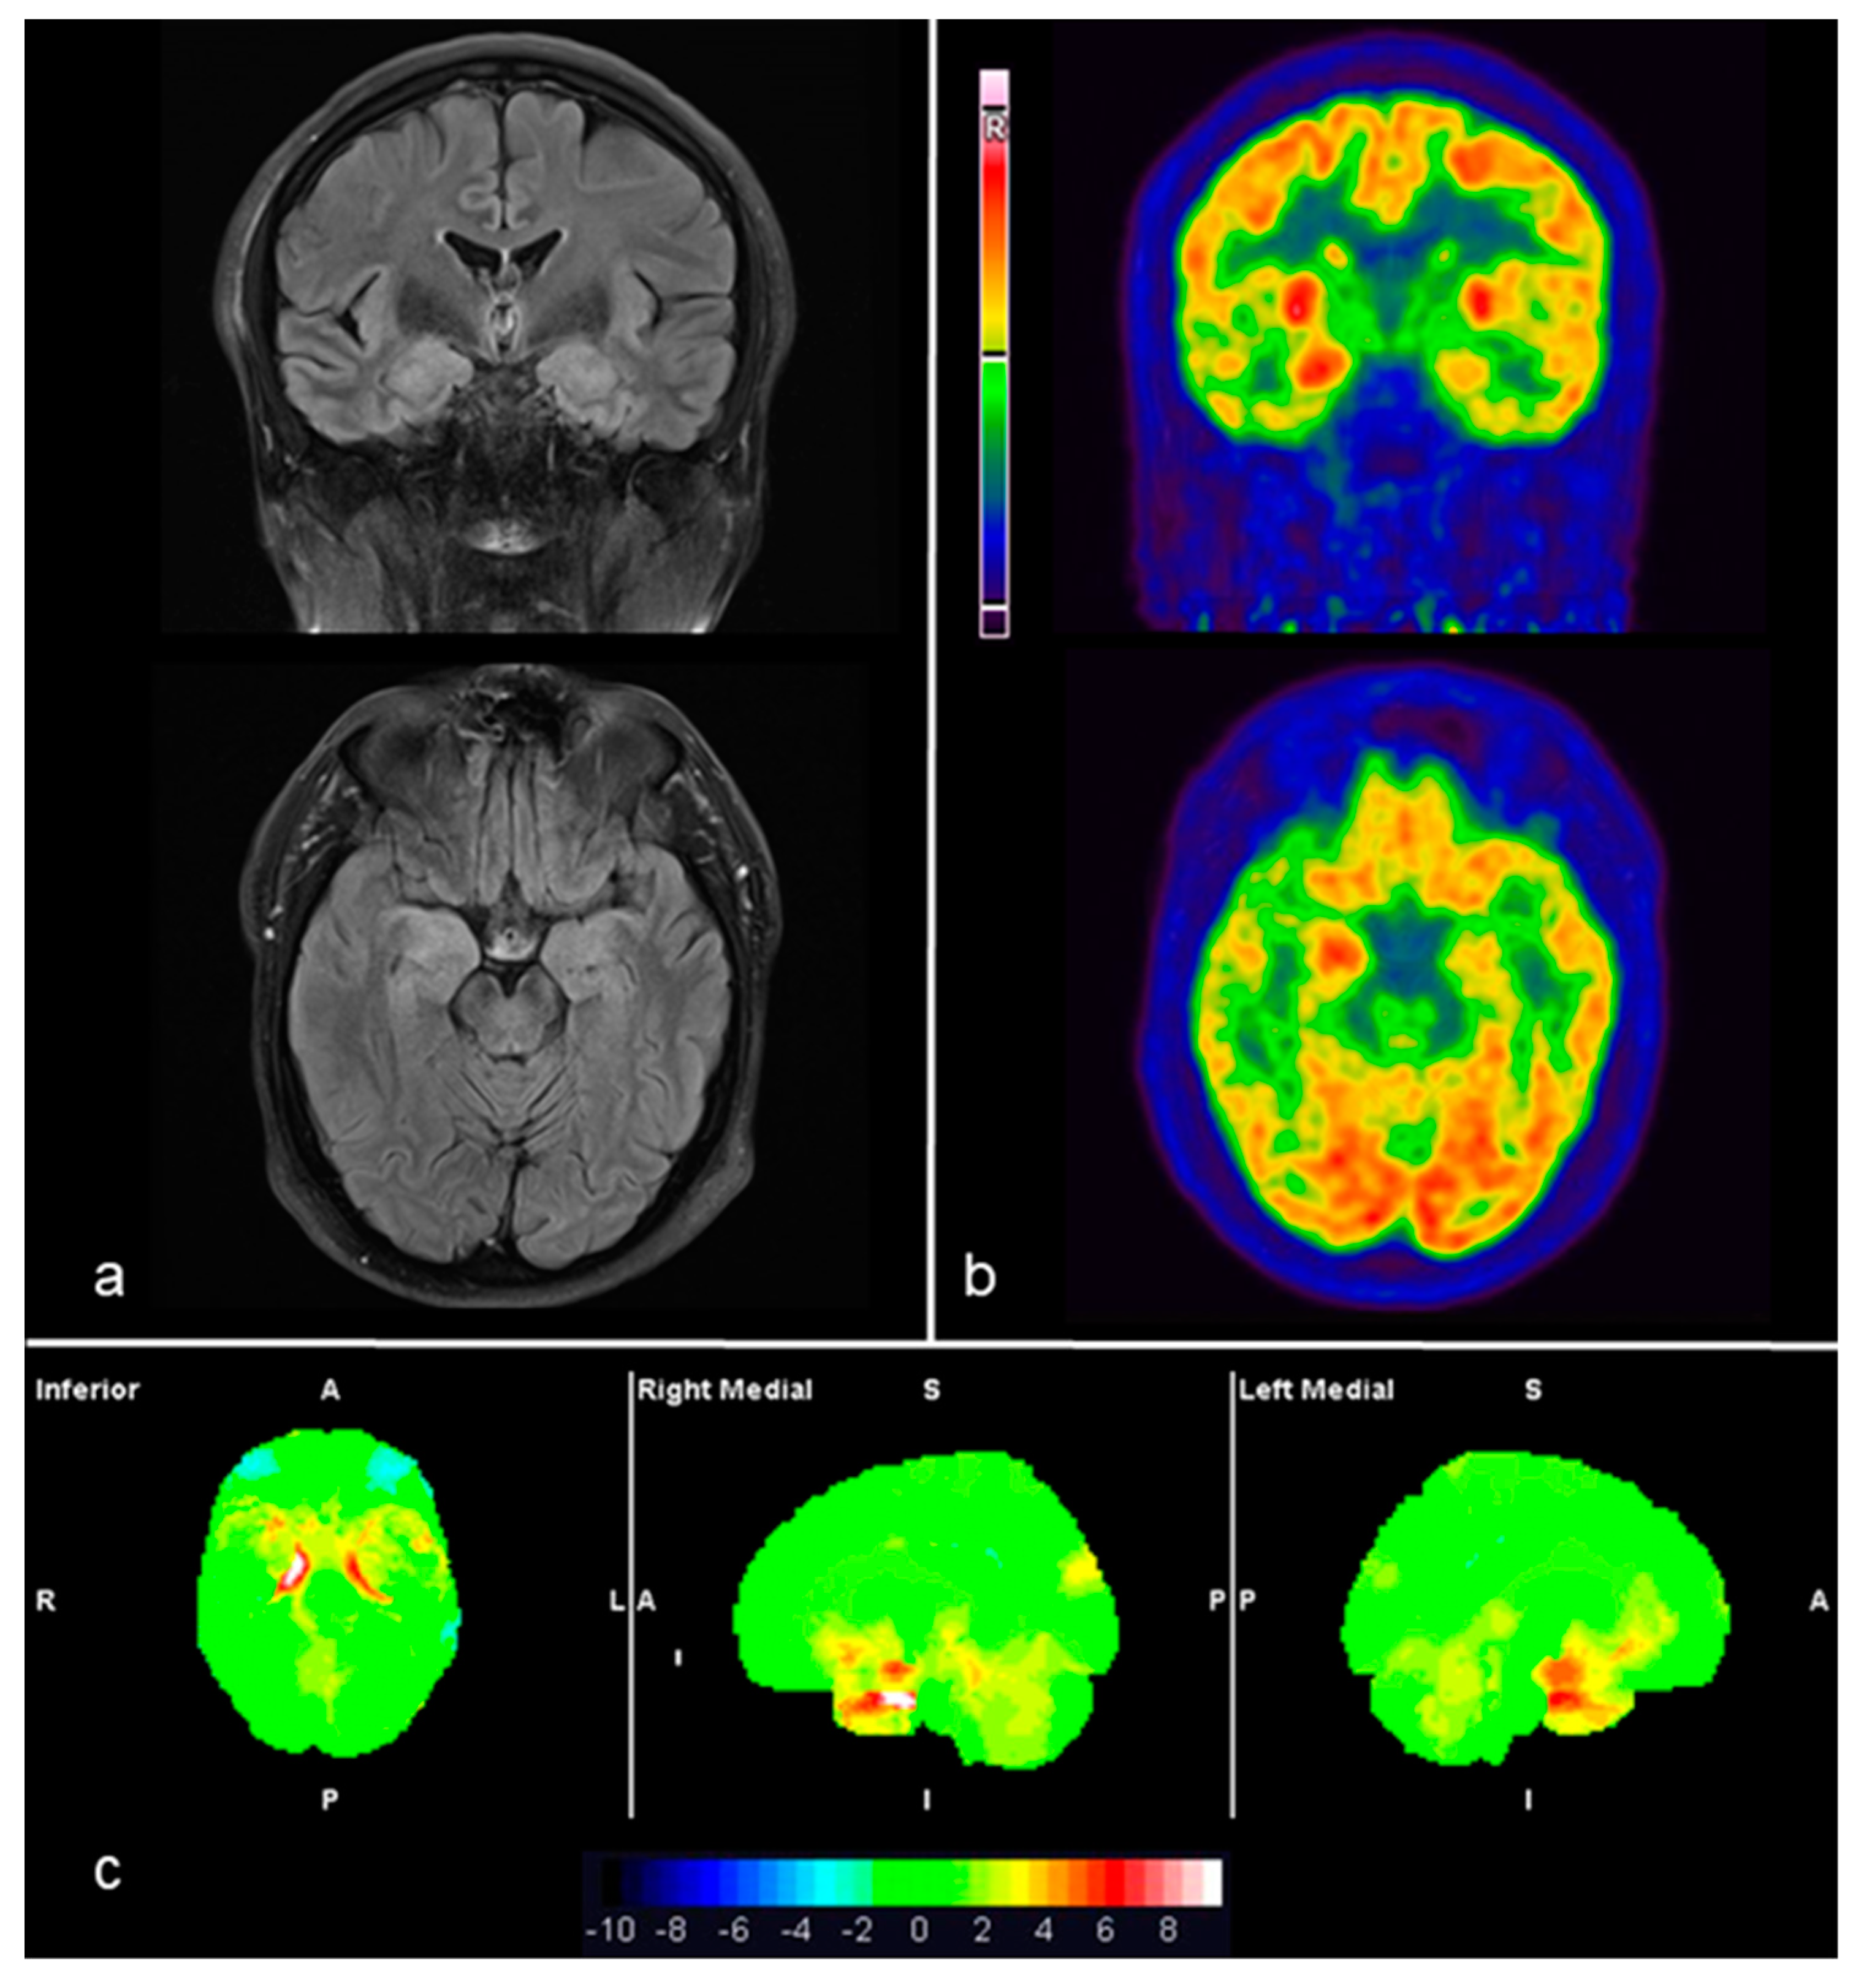

| 1 | NMDAR | L Frontal, L&R Temporal, Occipital, Motor cortex | L lateral Temporal | R MTL and lateral Temporal, L Frontal. R Motor cortex | R. Insula; L lateral Temporal, L&R Parietal; PC | Similar locations but more extended | Similar locations but more extended | L&R Frontal, R temporal, occipital, L&R Motor cortex | L temporal, medial Frontal, Insula, PC, L&R Parietal, Cerebellum | L&R Frontal, R temporal, occipital, L&R Motor cortex | L Temporal, medial Frontal, Insula, PC, L&R Parietal, Cerebellum |